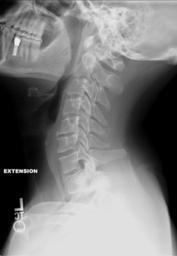

MAKE A MEME View Large Image Cervical Xray Extension.jpg en X-ray of cervical spine neck in extension bending backwards This series of x-rays were part of pre-surgical evaluation to help identify spinal instability Patient is a 37 year old male with a history of ...

Keywords: Cervical Xray Extension.jpg en X-ray of cervical spine neck in extension bending backwards This series of x-rays were part of pre-surgical evaluation to help identify spinal instability Patient is a 37 year old male with a history of multiple neck traumas with pain and muscle spasms and dental implant in lower jaw Excerpt from radiologist's report FINDINGS Five views of the cervical spine including flexion and extension were performed There is no evidence of fracture bone destruction or malalignment There are degenerative bone and is changes at C5-6 There is no evidence of cervical instability on the flexion and extension views The facet joints are well aligned Bony spurring is narrowing the C5-6 neural foramina bilaterally IMPRESSION Degenerative changes at C5-6 No evidence of instability Ragioagraphie aux rayons X du cou rachis cervical en extension vers l'arrière ; élément d'une série de radiographies faisant partie d'une évaluation pré-chirurgicale pour aider à identifier une éventuelle instabilité vertébrale chez un patient homme de 37 ans ayant des antécédents de traumatismes multiples cou avec spasmes et douleurs musculaires et implant dentaire à la mâchoire inférieure Le Rapport du radiologue dit RÉSULTATS Cinq vues de la partie cervicale de la colonne vertébrale ont été faites dont en flexion et en extension Il n'y a pas de signe de fracture de destruction osseuse ni de défaut d'alignement On observe un phénomène de gégénérescence osseuse des changements en C5-6 Il n'existe aucune preuve de l'instabilité du cou sur les radios montrant la flexion et l'extension Les facettes articulaires sont bien alignés Bony spurring is narrowing the C5-6 neural foramina bilaterally IMPRESSION Changements dégénératifs eu C5-6 Aucune preuve d'instabilité own medical image work for hire Stillwaterising 2010-04 Cervical XRayFlexionExtension jpg Magnification 0 4x converted from lossy DICOM file Cc-zero Lateral X-rays of the neck Dicom Human anatomy cervical vertebrae Anatomical terms of motion